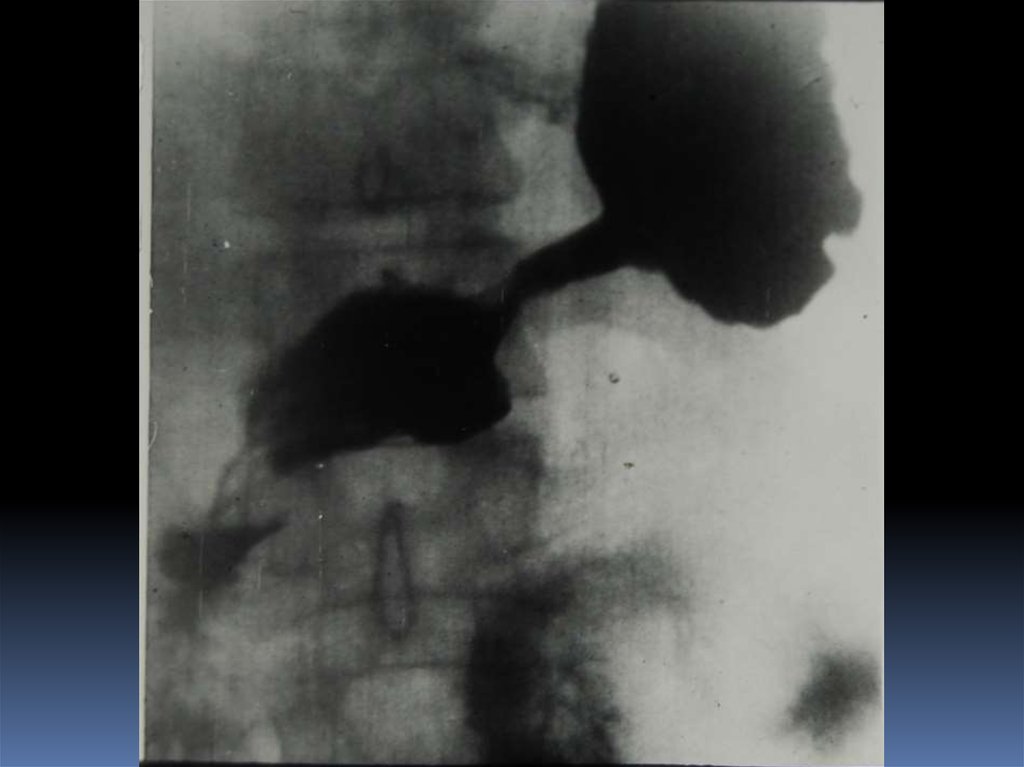

16. Рентгенодиагностика рака желудочно-кишечного тракта

Рентгенодиагностика

рака желудочнокишечного тракта